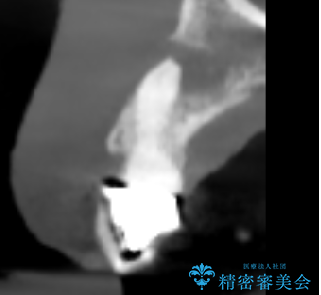

- 歯茎の大きな腫れを主訴に来院された患者様です。前歯5本にはブリッジが装着されていました。レントゲン検査より、右上3番に大きな根尖病巣が認められ、さらに左上1、2番の支台歯にも破折があったため、抜歯を行いました。その後、インプラントを3本埋入し、オールセラミッククラウンのブリッジで補綴しました。

術前のCT画像より、抜歯即時インプラントが可能と判断したため、抜歯と同時にインプラント埋入を行いました。術式にはセミルーナーフラップを用い、唇側の骨吸収を抑える目的でルートメンブレンテクニックを併用しました。